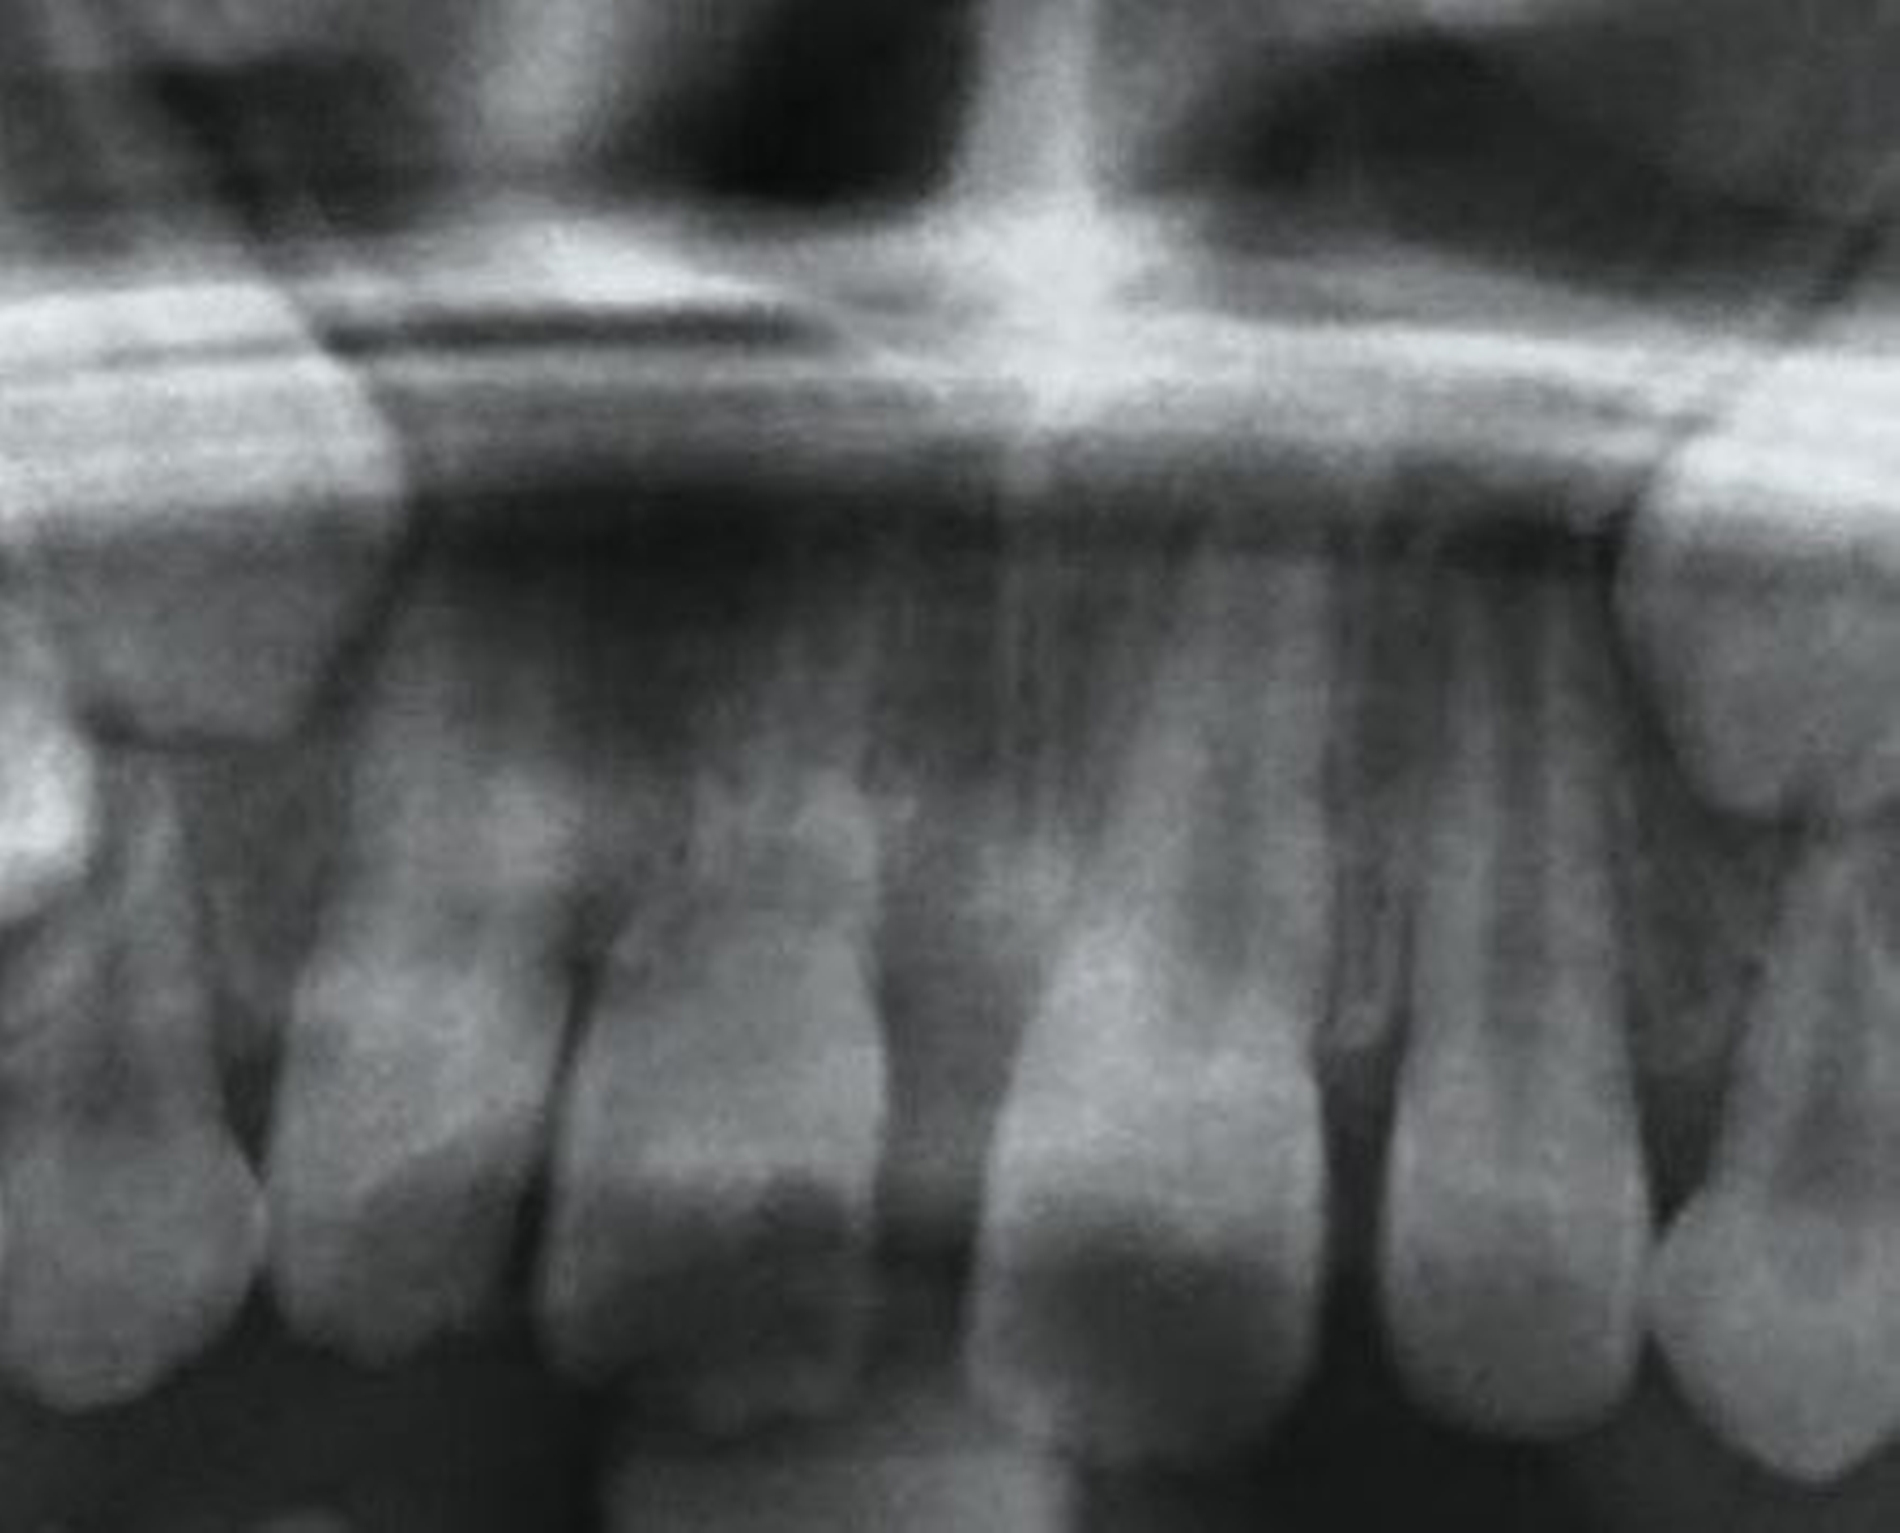

Dislokationsverletzungen von Zähnen können nicht selten mit einer Fraktur des zahntragenden Alveolarfortsatzes kombiniert sein, die auf Panoramaschichtaufnahmen oder gegebenenfalls weiterführenden Aufnahmen (Einzelzahnfilm, DVT) zur Darstellung kommen. Je nach Schweregrad wird hier zwischen einer partiellen Fraktur (Bruch der vestibulären oder oralen Alveolenwand) und einer vollständigen (Bruch der vestibulären und oralen Alveolenwand) im Sinne einer dislozierten beziehungsweise nicht dislozierten Fraktur des Alveolarfortsatzes unterschieden.

Klinisch findet sich neben häufigen, meist vertikalen Schleimhauteinrissen gegebenenfalls eine tastbare Stufenbildung (Abbildung 6). Dislozierte Alveolarfortsatzfrakturen gehen in der Regel mit einer Okklusionsstörung einher, die Sensibilität der betroffenen Zähne geht dabei häufig verloren. Die Therapie der Alveolarfortsatzfrakturen weist einige Besonderheiten auf, die in der entsprechenden Empfehlung der Leitlinie aufgeführt sind.